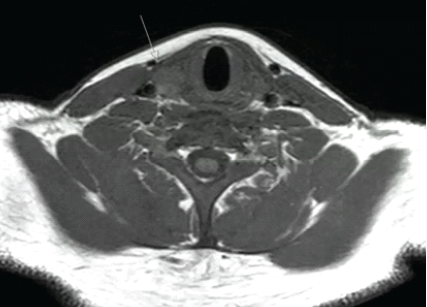

Magnet resonance imaging confirmed in sagittal T2-weighted sequences bilateral total distal quadriceps tendon rupture at the patella insertion site (Fig. 1 and 2). A parathyroid adenoma was diagnosed in axial T2-weighted sequence (Fig. 3).

Figure 3: Magnet resonance imaging of the neck demonstrating a solitary hypoechoic nodule consistent with parathyroid adenoma.